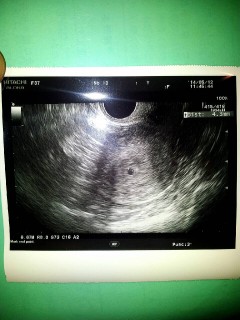

4.3mmで胎嚢確認。

4w後半~5w前半と(^o^)